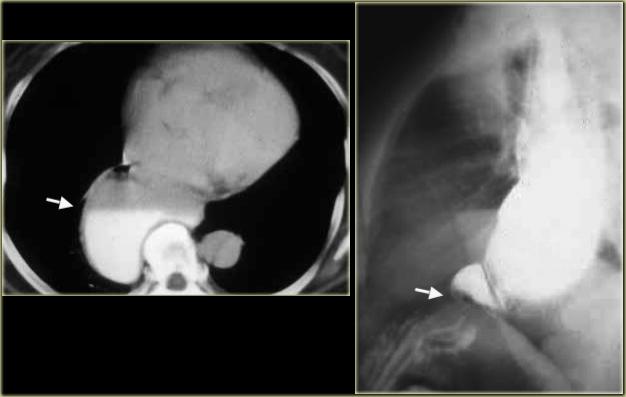

Bên trái là một ví dụ khác về túi thừa trên cơ hoành.

CT cho thấy túi thừa kích thước lớn (mũi tên) lan sang phải, ngay trên cơ hoành.

Bệnh nhân này không có triệu chứng.